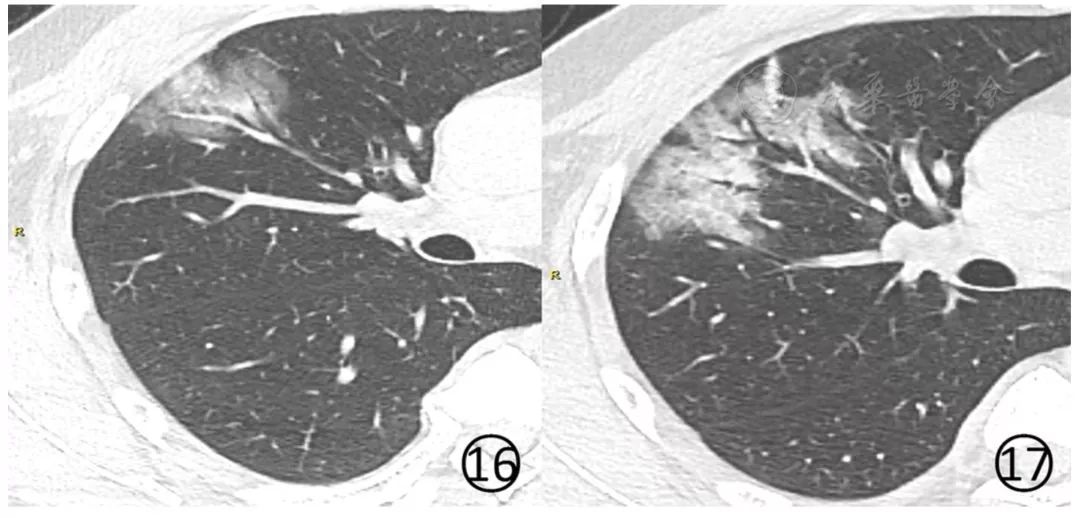

原有病变多数病灶范围扩大,病灶内出现大小、程度不等的实变(图16,图17),有结节和晕征、实变病灶内可见空气支气管征。

图16,17男,44岁。基线(图16)及4d后(图17)肺CT平扫肺窗显示右肺上叶前段病变范围扩大,局部变密实,并可见空气支气管征,支气管血管束增粗